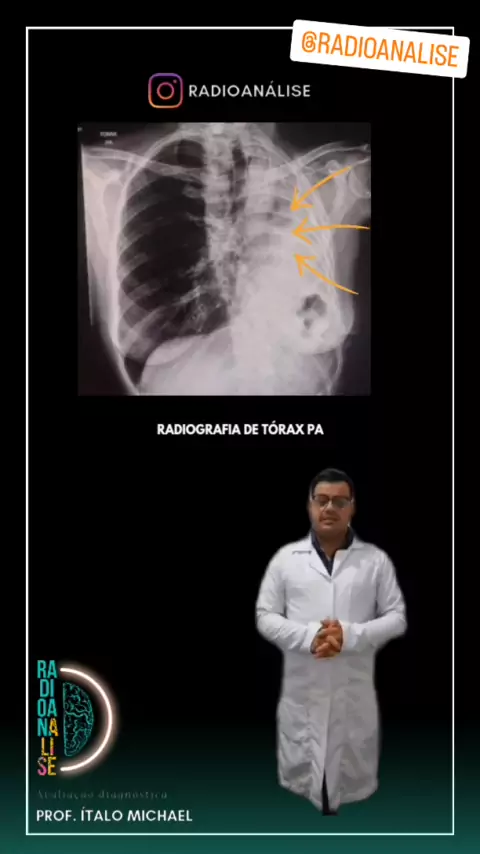

tudo bem? Eu me chamo Ítalo Michael sou técnico em radiologia,E hoje vamos falar um pouquinho sobre raio-x do tórax e também falar sobre anatomia radiológica e patologia apresentada na imagem,mas Lembrando que quem fecha o diagnóstico são os médicos não sou eu técnico e nem os tecnólogos em radiologia o meu intuito é te ensinar a interpretar este tipo de imagem em radiologia. TR° Ítalo Michael CRTR -07244t #raiox #anatomia #radiologia #medicinaporamor #viral

raio x de torax #med #T_Enfermagem #radiology

como carcular o índice cardiotóracico @tr.italomichael CRTR-PR 07244T #med #radiology #RaioXd #cardiologia #medicina